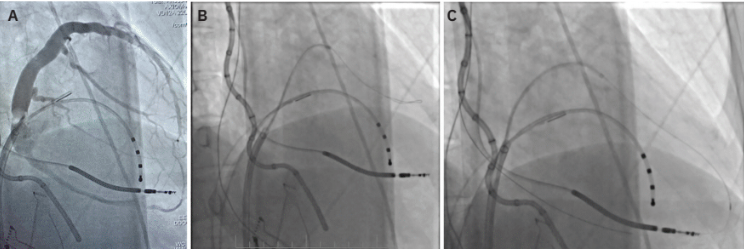

An example of a VT ablation performed using cardiac imaging is shown in Figure 1. A cardiac CT processed by inHEART is accompanied by an intracardiac ultrasound image. This patient had a large inferobasal left ventricular aneurysm with recurrent VT despite extensive endocardial ablation. She was brought back to the EP laboratory, and epicardial access was obtained using CO2 insufflation via intentional coronary vein exit (Figures 2A-C), as described by Silberbauer.20 The area of scar targeted for epicardial ablation is shown in Figure 3. The patient has been free of VT for over 12 months since her epicardial ablation and without any complications from the procedure.

Another example of VT ablation in a patient with hypertrophic cardiomyopathy is shown in Figure 4. Deep septal scar is demonstrated by late iodine enhancement on cardiac CT processed with inHEART. Ablation in this area terminated the patient’s clinical VT.